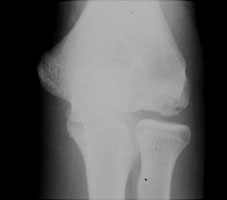

Resulting from valgus stress, fractures of the medial epicondyle of the humerus (little-leaguer's elbow) are really avulsion injuries. The medial epicondyle (or apophysis) of the humerus is injured by repeated violent contractions of the forearm flexor muscles which arise at this site. This is particularly seen in curveball and slider pitches; these motions result in strong valgus forces being applied at the medial epicondyle.

- Click on the image for a larger versionAAP radiograph of the elbow. This shows a lucency extending through the medial epicondyle of the humerus, typical for the appearance of little-leaguer's elbow.